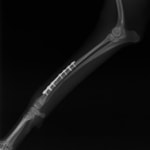

トイプードル 右遠位橈尺骨短斜骨折のALPSによる内固定

当院ではAdvanced Locking plate system(ALPS)と、Locking compression plate system(LCPS)という骨接合法で骨折症例の治療を行っています。

従来型のプレートのように広い面積で骨と接するプレートを用いて固定を行った場合、プレート下の骨はプレートとの接触面において血行が絶たれ壊死し、それがリモデリングされると骨密度が低下する。この骨密度の低下防ぐために、骨折部局所への血行を温存することの重要性が近年改めて認識されるようになってきている。Advaed Locking Plate System (ALPS)は従来型のプレートシステムの欠点を改良し、より使いやすく、より骨への血行を阻害しないようにというコンセプトで作られた。

Advanced Locking Plate System の特徴

- 骨への血行障害は最小限である

- 上下左右にベンディング可能でより3次元的な成形が可能

- すべての部位においてプレート強度は均一である

- ロッキングスクリューと圧着型スクリュー(皮質骨スクリュー)の双方が使用できる

- ダイナミックコンプレッション機能

- 生体親和性の高いチタン製

- トイ犬種から馬まで応用できるサイズ展開がある